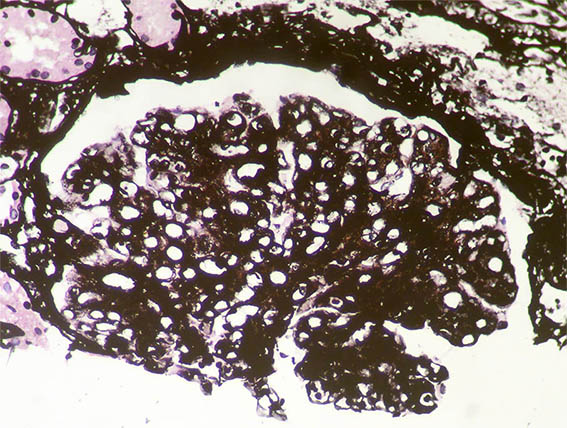

Figure 6. Methenamine-silver stain, X400.